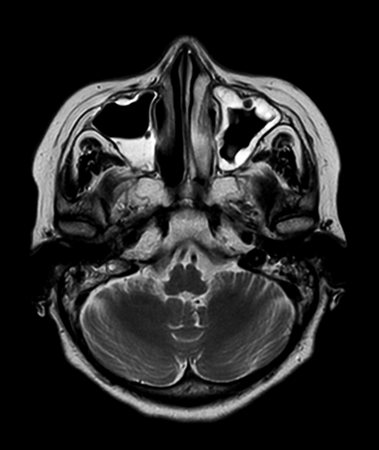

Axial mDIXON XD - T1w TSE (Water only)